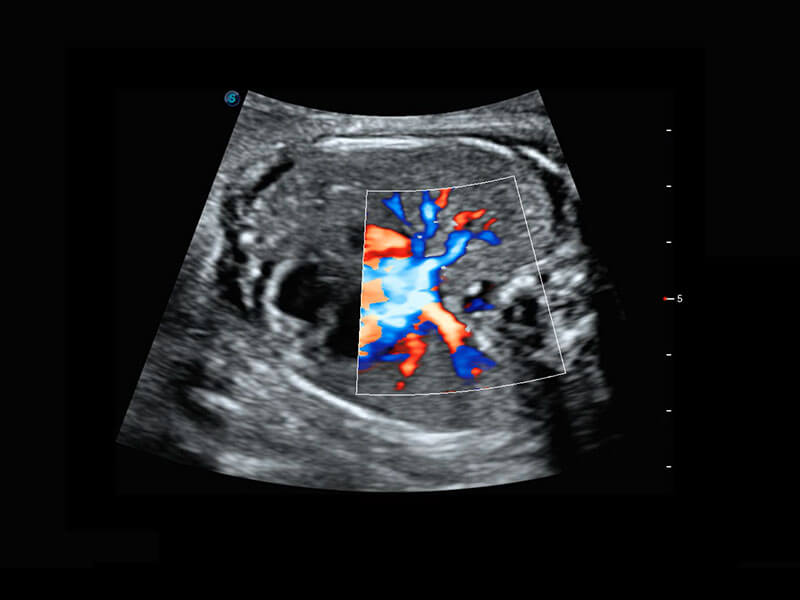

P60为盆底超声检查提供应用方案,多种腔内及腹部容积探头提供从二维、三维到四维的优异图像品质,实时快速三维容积数据获取,专业的测量工具包等人性化设计,为超声医生诊断提供有力保障。

Lev.Hiat A-r: 16.33 cm2

Lev.Hiat H-r: 53.70 mm

Lev.Hiat W-r: 43.96 mm

Lt-LUG-r: 24.16 mm

Rt-LUG-r: 19.94 mm

能够简化盆底检查的操作流程,可在二维模式及三维成像模式下实现一键自动提取出标准切面、自动识别当前切面、自动测量,提升盆底检查的高效性,同时也能让青年医生快捷的获得准确的检查结果。